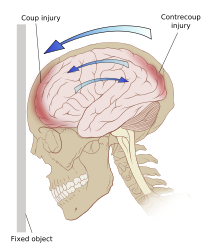

Even in the absence of an impact, significant acceleration or deceleration of the head can cause TBI; however in most cases, a combination of impact and acceleration is probably to blame.[66] Forces involving the head striking or being struck by something, termed contact or impact loading, are the cause of most focal injuries, and movement of the brain within the skull, termed noncontact or inertial loading, usually causes diffuse injuries.[67] The violent shaking of an infant that causes shaken baby syndrome commonly manifests as diffuse injury.[68] In impact loading, the force sends shock waves through the skull and brain, resulting in tissue damage.[66] Shock waves caused by penetrating injuries can also destroy tissue along the path of a projectile, compounding the damage caused by the missile itself.[32]

Damage may occur directly under the site of impact, or it may occur on the side opposite the impact (coup and contrecoup injury, respectively).[65] When a moving object impacts the stationary head, coup injuries are typical,[69] while contrecoup injuries are usually produced when the moving head strikes a stationary object.[70]